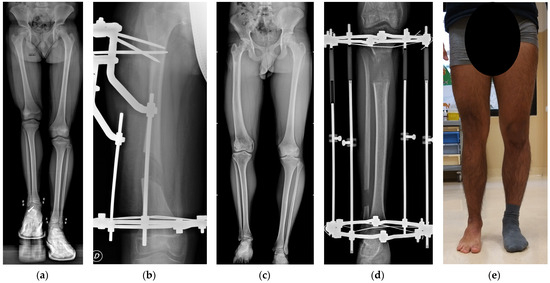

2. Materials and Methods

3.3. Surgical Parameters and Outcomes